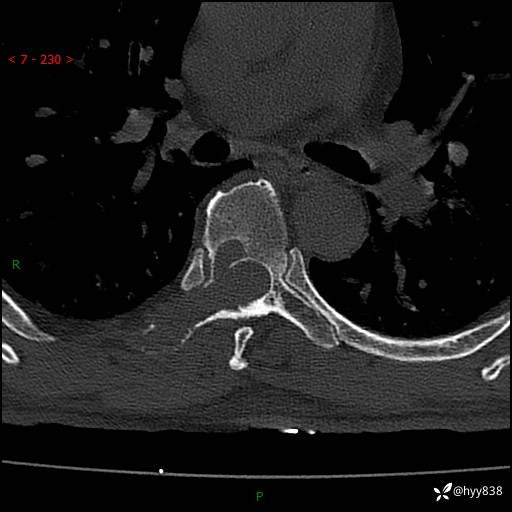

胸椎CT平扫(骨窗+软组织窗)